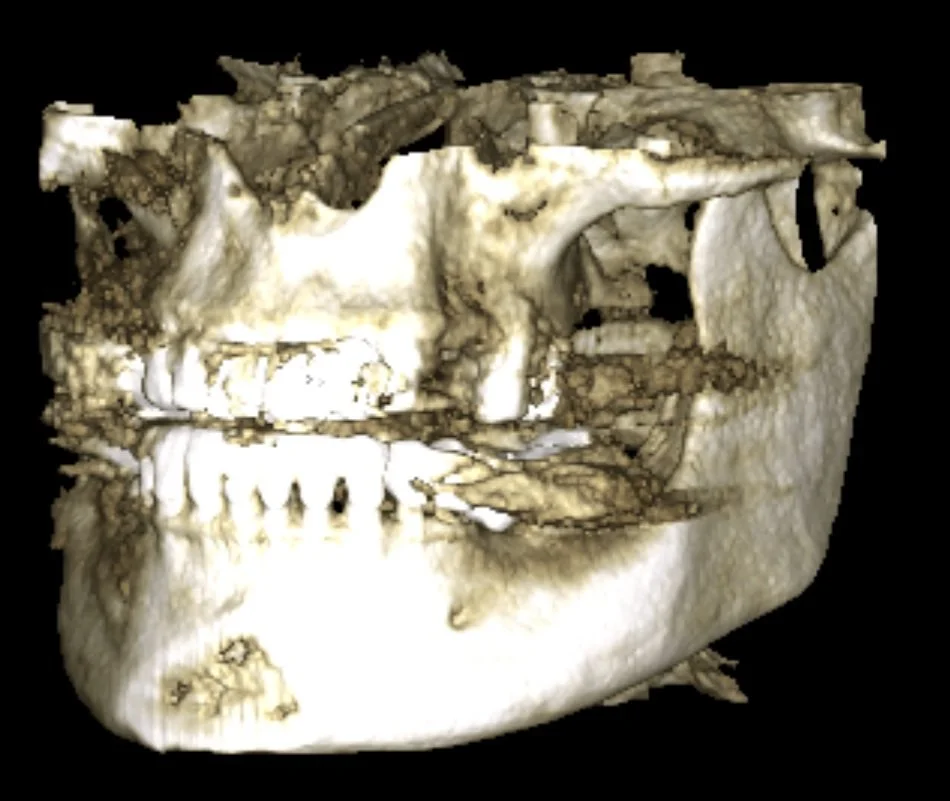

A 3D X-ray (CBCT) was taken to check the bone

The scan showed that the bone space was limited, so the implants had to be placed very accurately.

Using specialized software, the CBCT and intraoral scans were merged into a single digital model. The missing teeth were digitally designed in their ideal position, and two high-quality implants were carefully planned according to the final crowns and available bone — without the need for bone grafting.